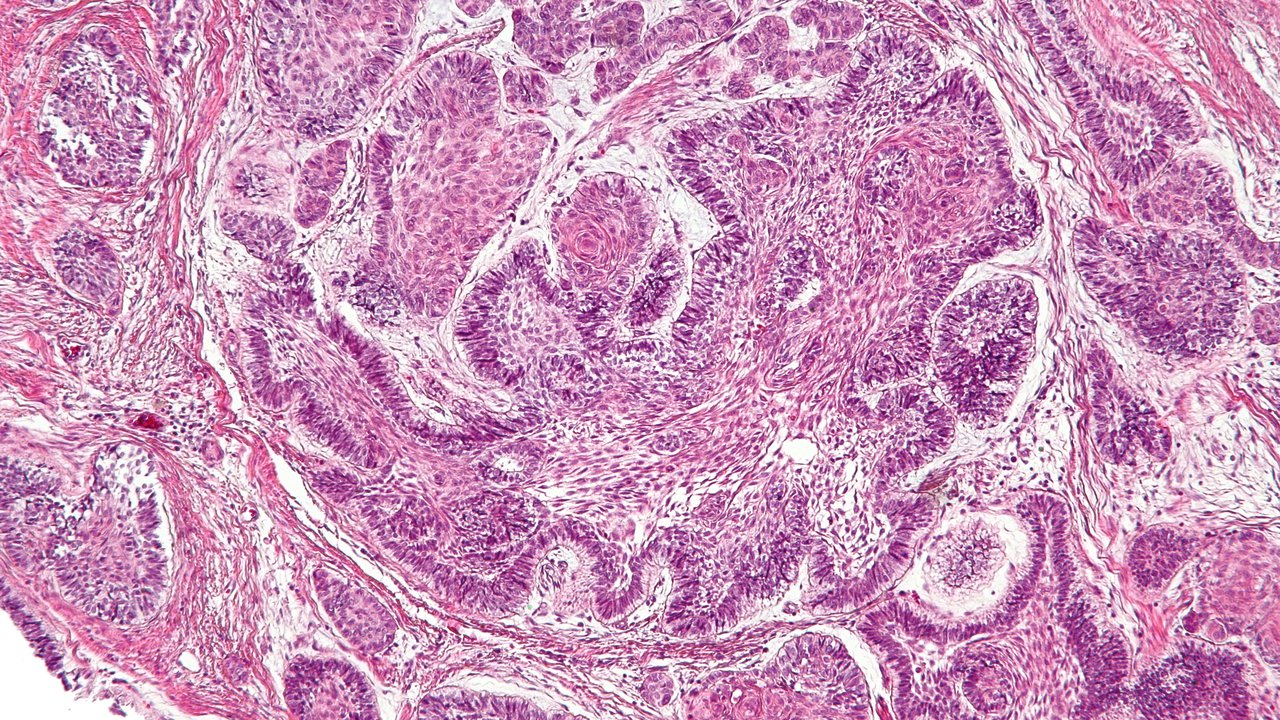

Figure 4(1) Ameloblastoma The tumor is composed of proli… Flickr Ameloblastoma Hereditary Web ameloblastomas are benign but locally invasive neoplasms which may grow to massive proportions and cause. Web ameloblastoma is a rare kind of tumor that starts in your jaw, often near your wisdom teeth or molars. Web ameloblastoma is characterized by an abnormal growth in the sinus area or jaw, often at the site of the third molar. Web ameloblastomas. Ameloblastoma Hereditary.